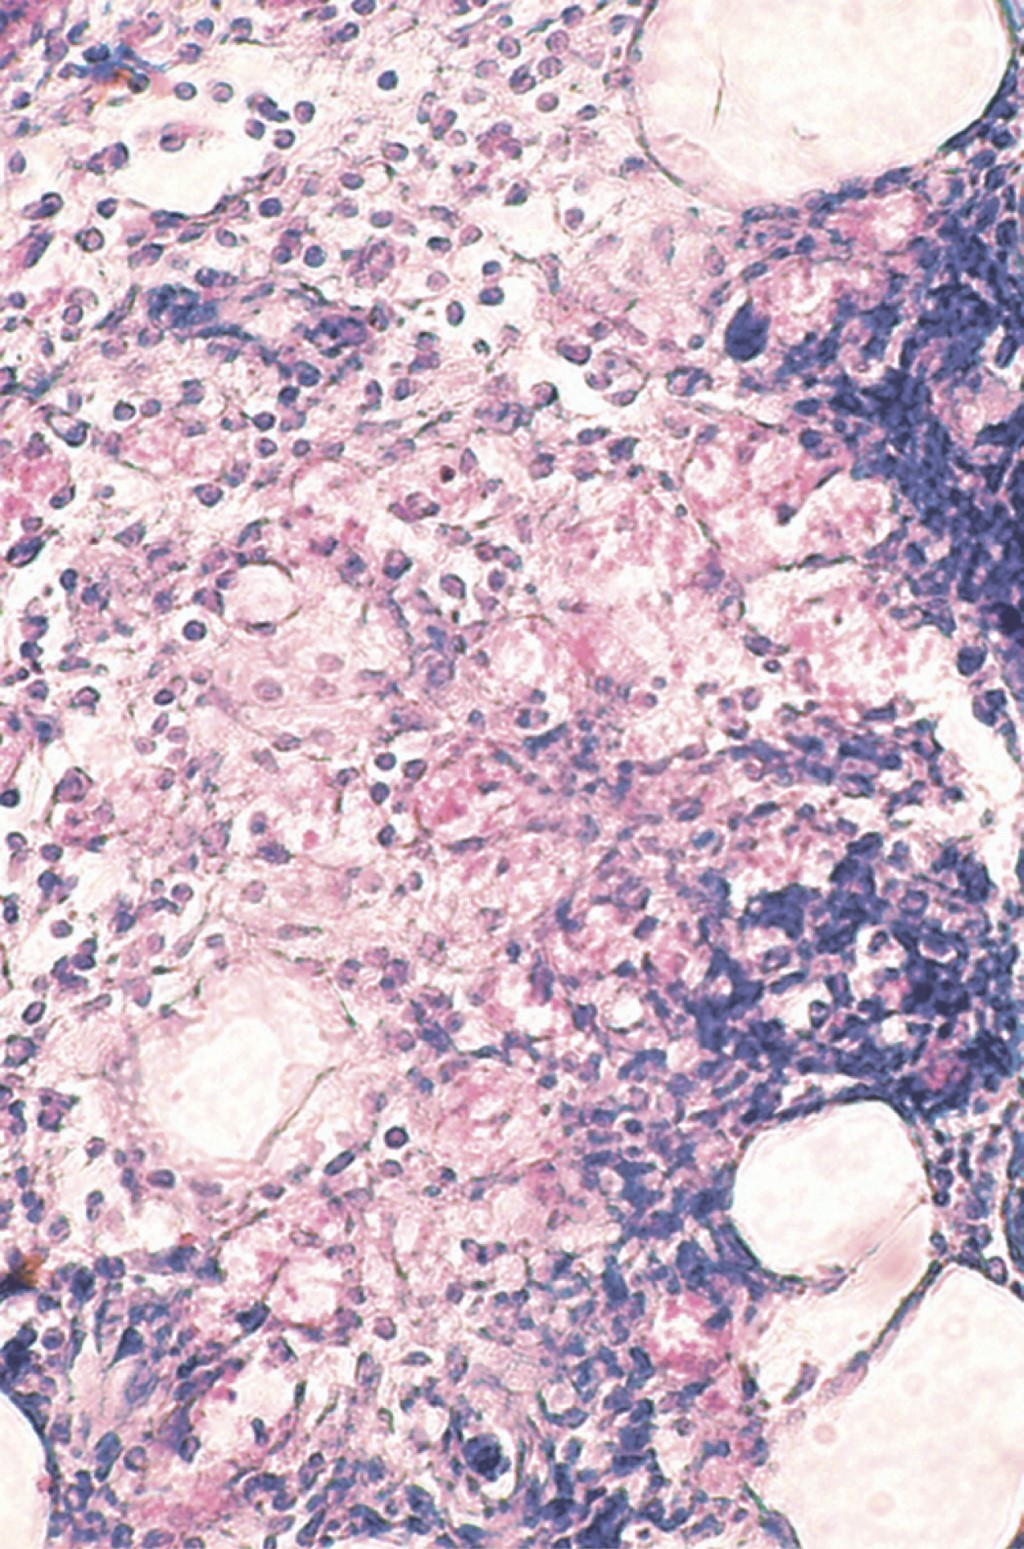

Se realiza biopsia incisional y el estudio histopatológico con tinción de rutina muestra: epidermis atrófica con hiperqueratosis ortoqueratósica, formación de tapones córneos e hiperpigmentación de la capa basal. En algunas zonas de la dermis superficial se observa la presencia de edema entre las fibras colágenas así como infiltrados moderados focales que tienden a rodear algunos vasos dilatados y congestionados. Estos infiltrados aumentan en intensidad y se observan ocupando la dermis media y profunda, e incluso hasta tejido celular subcutáneo. Están constituidos por abundantes histiocitos vacuolados, mismos que son más evidentes en las partes profundas del corte; además se aprecian linfocitos, histiocitos y numerosos polimorfonucleares que se ubican de manera predominante en las partes profundas de la epidermis y tejido celular subcutáneo, disponiéndose al nivel de los lóbulos grasos. Se aprecia edema en algunos sitios de la dermis profunda. Los infiltrados también tienden a rodear en algunos sitios a fibras nerviosas engrosadas. La tinción para bacilos fue positiva (Figuras 4, 5 y 6).

Figura 4